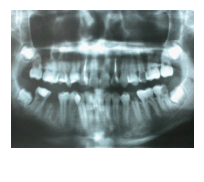

43歲女性病人,如圖1A所示。病人由其他醫師轉診來拔除左下顎嚴重蛀牙的第二大臼齒與阻生智齒,理論上如果拔除此第二大臼齒後,必須以人工植牙重建之,但是病人有經濟上的考量,因此與病人討論過後,決定將同時欲拔除的 阻生智齒移植入第二大臼齒齒槽,雖然病人年紀稍大,仍值得一試,圖1B 是術後一個月的X光片,由於病人年紀較大,智齒在植入缺牙區域時,已同時作根管治療,圖1C是術後四個月的X光片,根管內充填的是Vitapex(Ca(OH)2),圖1D是術後一年四個月後的X光片,智齒牙根尖的骨頭已經全部再生回來,而且牙根無黏連的情形,臨床上牙齒動搖度小於1,牙周組織健康,而其前面的第一大臼齒情況良好,咬合正常。

圖1B

圖1C

圖1D